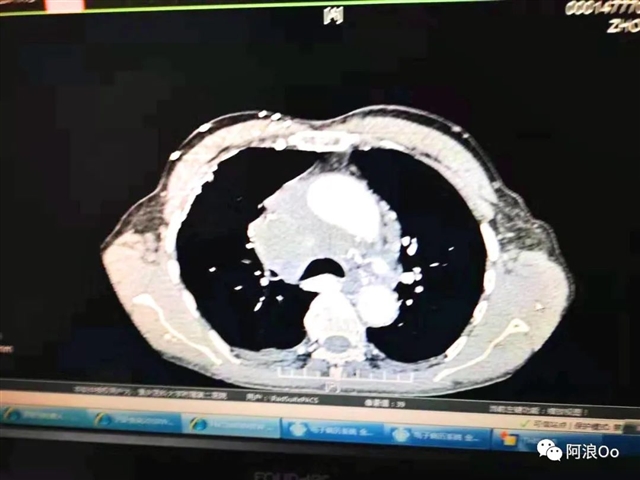

国内首位!李长毅开展电刀辅助下经气管纵隔活检钳取活检技术(Cautery Assist Transbronchial For cep Biopsy,Ca-TBFB):超声支气管镜引导,经过气管软骨环用针形电刀切开气管粘膜进入纵隔,以活检钳进行纵隔钳取活检。相对于传统TBNA和eBUS-TBNA,能够取得大块组织标本,对于纵隔良性疾病、淋巴瘤具有明显优势。淋巴结坏死明显,多次eBUS-TBNA拿不到病理依据,可以作为备选技术。